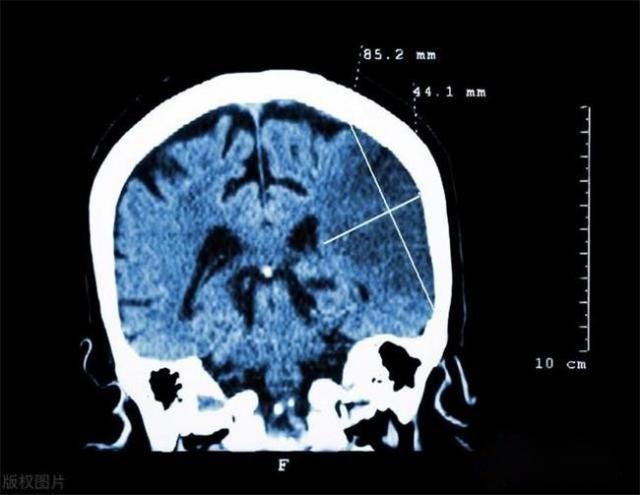

简要回答 醒来时视力模糊,舌头发麻、睡觉时流口水,口齿不清、总打哈欠,手脚麻木。脑梗死是一种突发性的疾病,它发展迅速,抢救的时间非常有限。一旦发生脑梗死,它可能会导致偏瘫、痴呆等严重后果,而且脑梗死还具有高死亡率的特点。 一、脑梗死的发病原因是什么 1. 动脉粥样硬化是其中一个主要原因,而动脉粥样硬化的形成与高脂血症、糖尿病、高血压、吸烟、酗酒等因素密切相关。 2. 房颤。随着房颤 患者 数量的不断增加,我们对于房颤治疗的认知仍然不足。房颤是一种心律失常的情况,容易导致血栓...